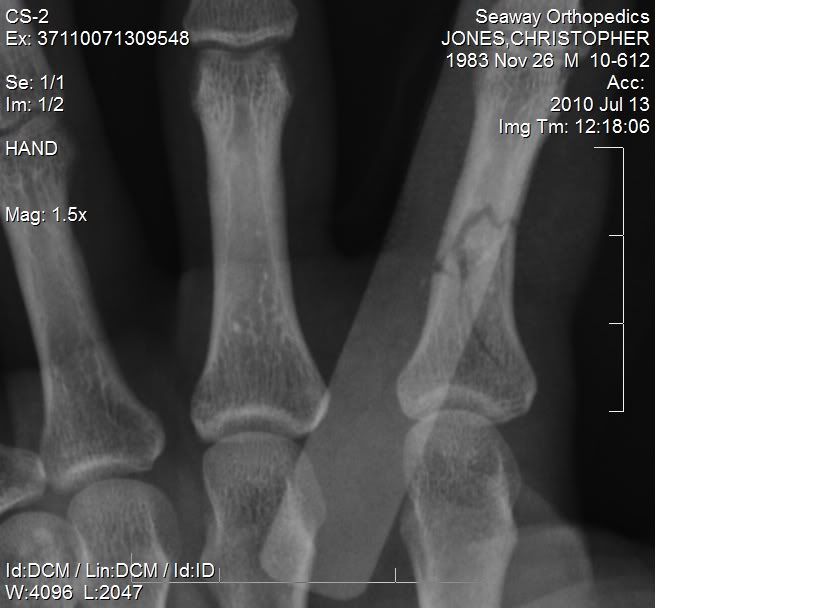

well went to the dr on friday and i found out that the finger hasnt started to heal at all, the tendon is stuck to the plate, the bone hasnt even started to heal back together, PT is doing more harm then good. as soon as i get a call from the dr when the appointment is i will be heading to Burlington VT to have a "hand surgeon" do another surgery on my had!

sorry for the crappy cell pic, but you can see the plate and where there is no bone formation at the break.